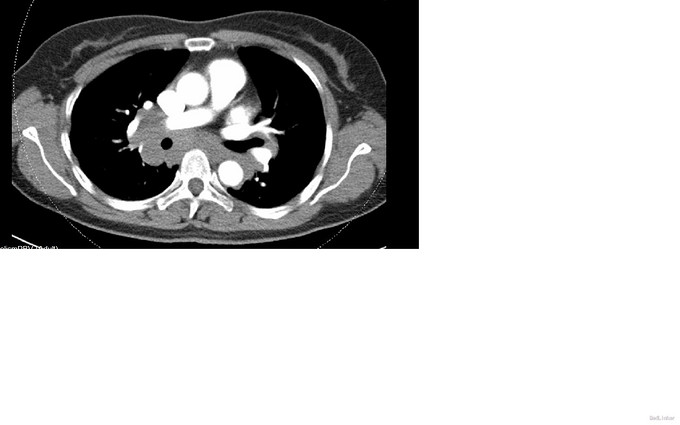

CT提示纵隔多发的巨大淋巴结增生,考虑结节病可能

放射科也考虑结节病可能 收住院行EBUS-TNBA穿刺 做了两次穿刺均未找到癌细胞,考虑肉芽组织

进一步扫全身多处的淋巴结、均有肿大 初步排除cancer,转呼吸内科进一步诊治。 呼吸内科的EBUS-TBNA技术的日趋成熟,对于外科术前分期、判断非常有价值。随着诊疗的个体化呼声越来越高,内、外、病理、影像、放化疗组成的综合肺部肿瘤诊治中心发展前景很大